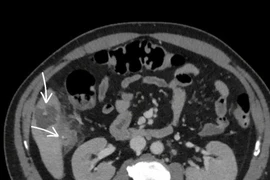

Người đàn ông 58 tuổi áp xe gan vì nuốt phải xương cá

Trong ăn uống cần đặc biệt lưu ý, tránh để xương lọt vào đường tiêu hóa, vì có thể gây biến chứng nặng nề, thậm chí nguy hiểm tính mạng.